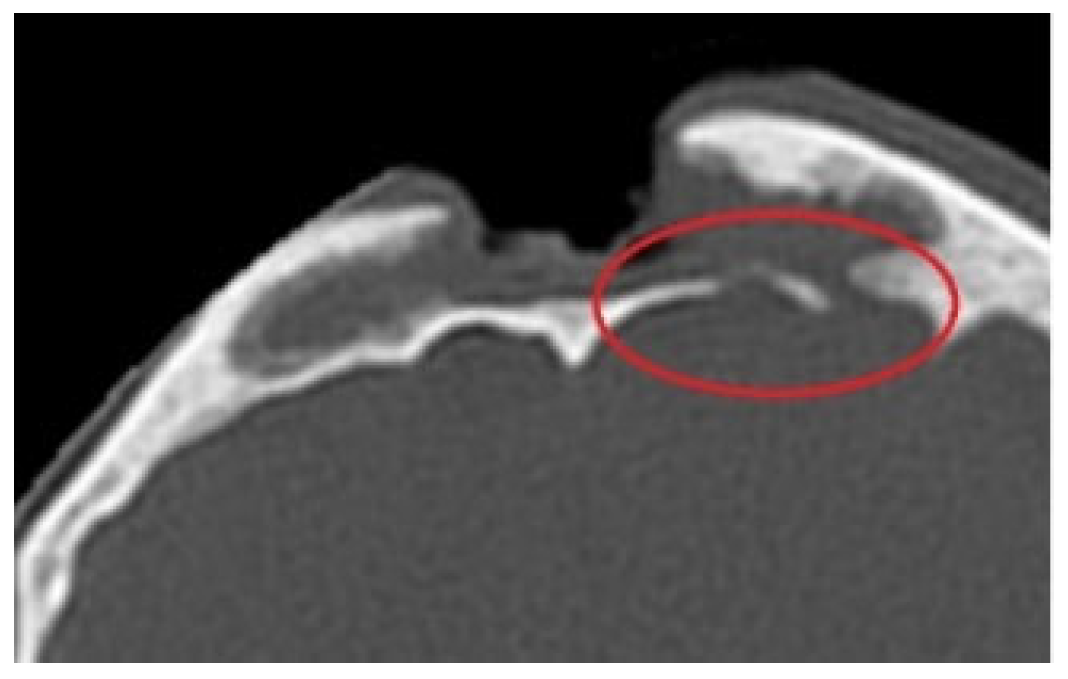

The patient underwent a non-contrast CT scan (Revolution Evo system, 64 rows, GEHealthcare). The obtained image revealed a defect of bone and soft tissue in the glabella area, about 3 cm in diameter, and an overgrowth of bone tissue across the entire width of the nasofrontal duct. (Figure 3A,B)

Figure 3. (A) Condition after the first CT scan-sagittal plane. (B) Condition after the first CT scan-transverse plane. (C) CT scan 14 days after first procedure-sagittal plane. (D) CT scan 14 days after first procedure-transverse plane.

Fourteen days following the laryngological procedure, the created canal was found to be overgrown and the nasofrontal duct lacked patency. A repeat CT scan of the facial part of the cranium confirmed that the canal was overgrown with soft tissue compared with the previous examination (Figure 3C,D).